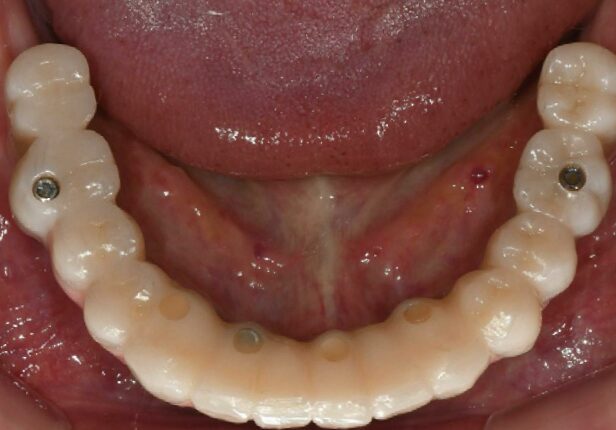

Caso Mandibular completo

caso de estudo

Antes da cirurgia

Panorâmica pré-cirúrgica

Colocação do implante

Posicionamento AXA

Panorâmica pós-cirúrgica

Coroa provisória logo após a colocação (1.ª: Capa)

Coroa provisória após 1 mês (2.ª)

Coroa provisória após 10 meses